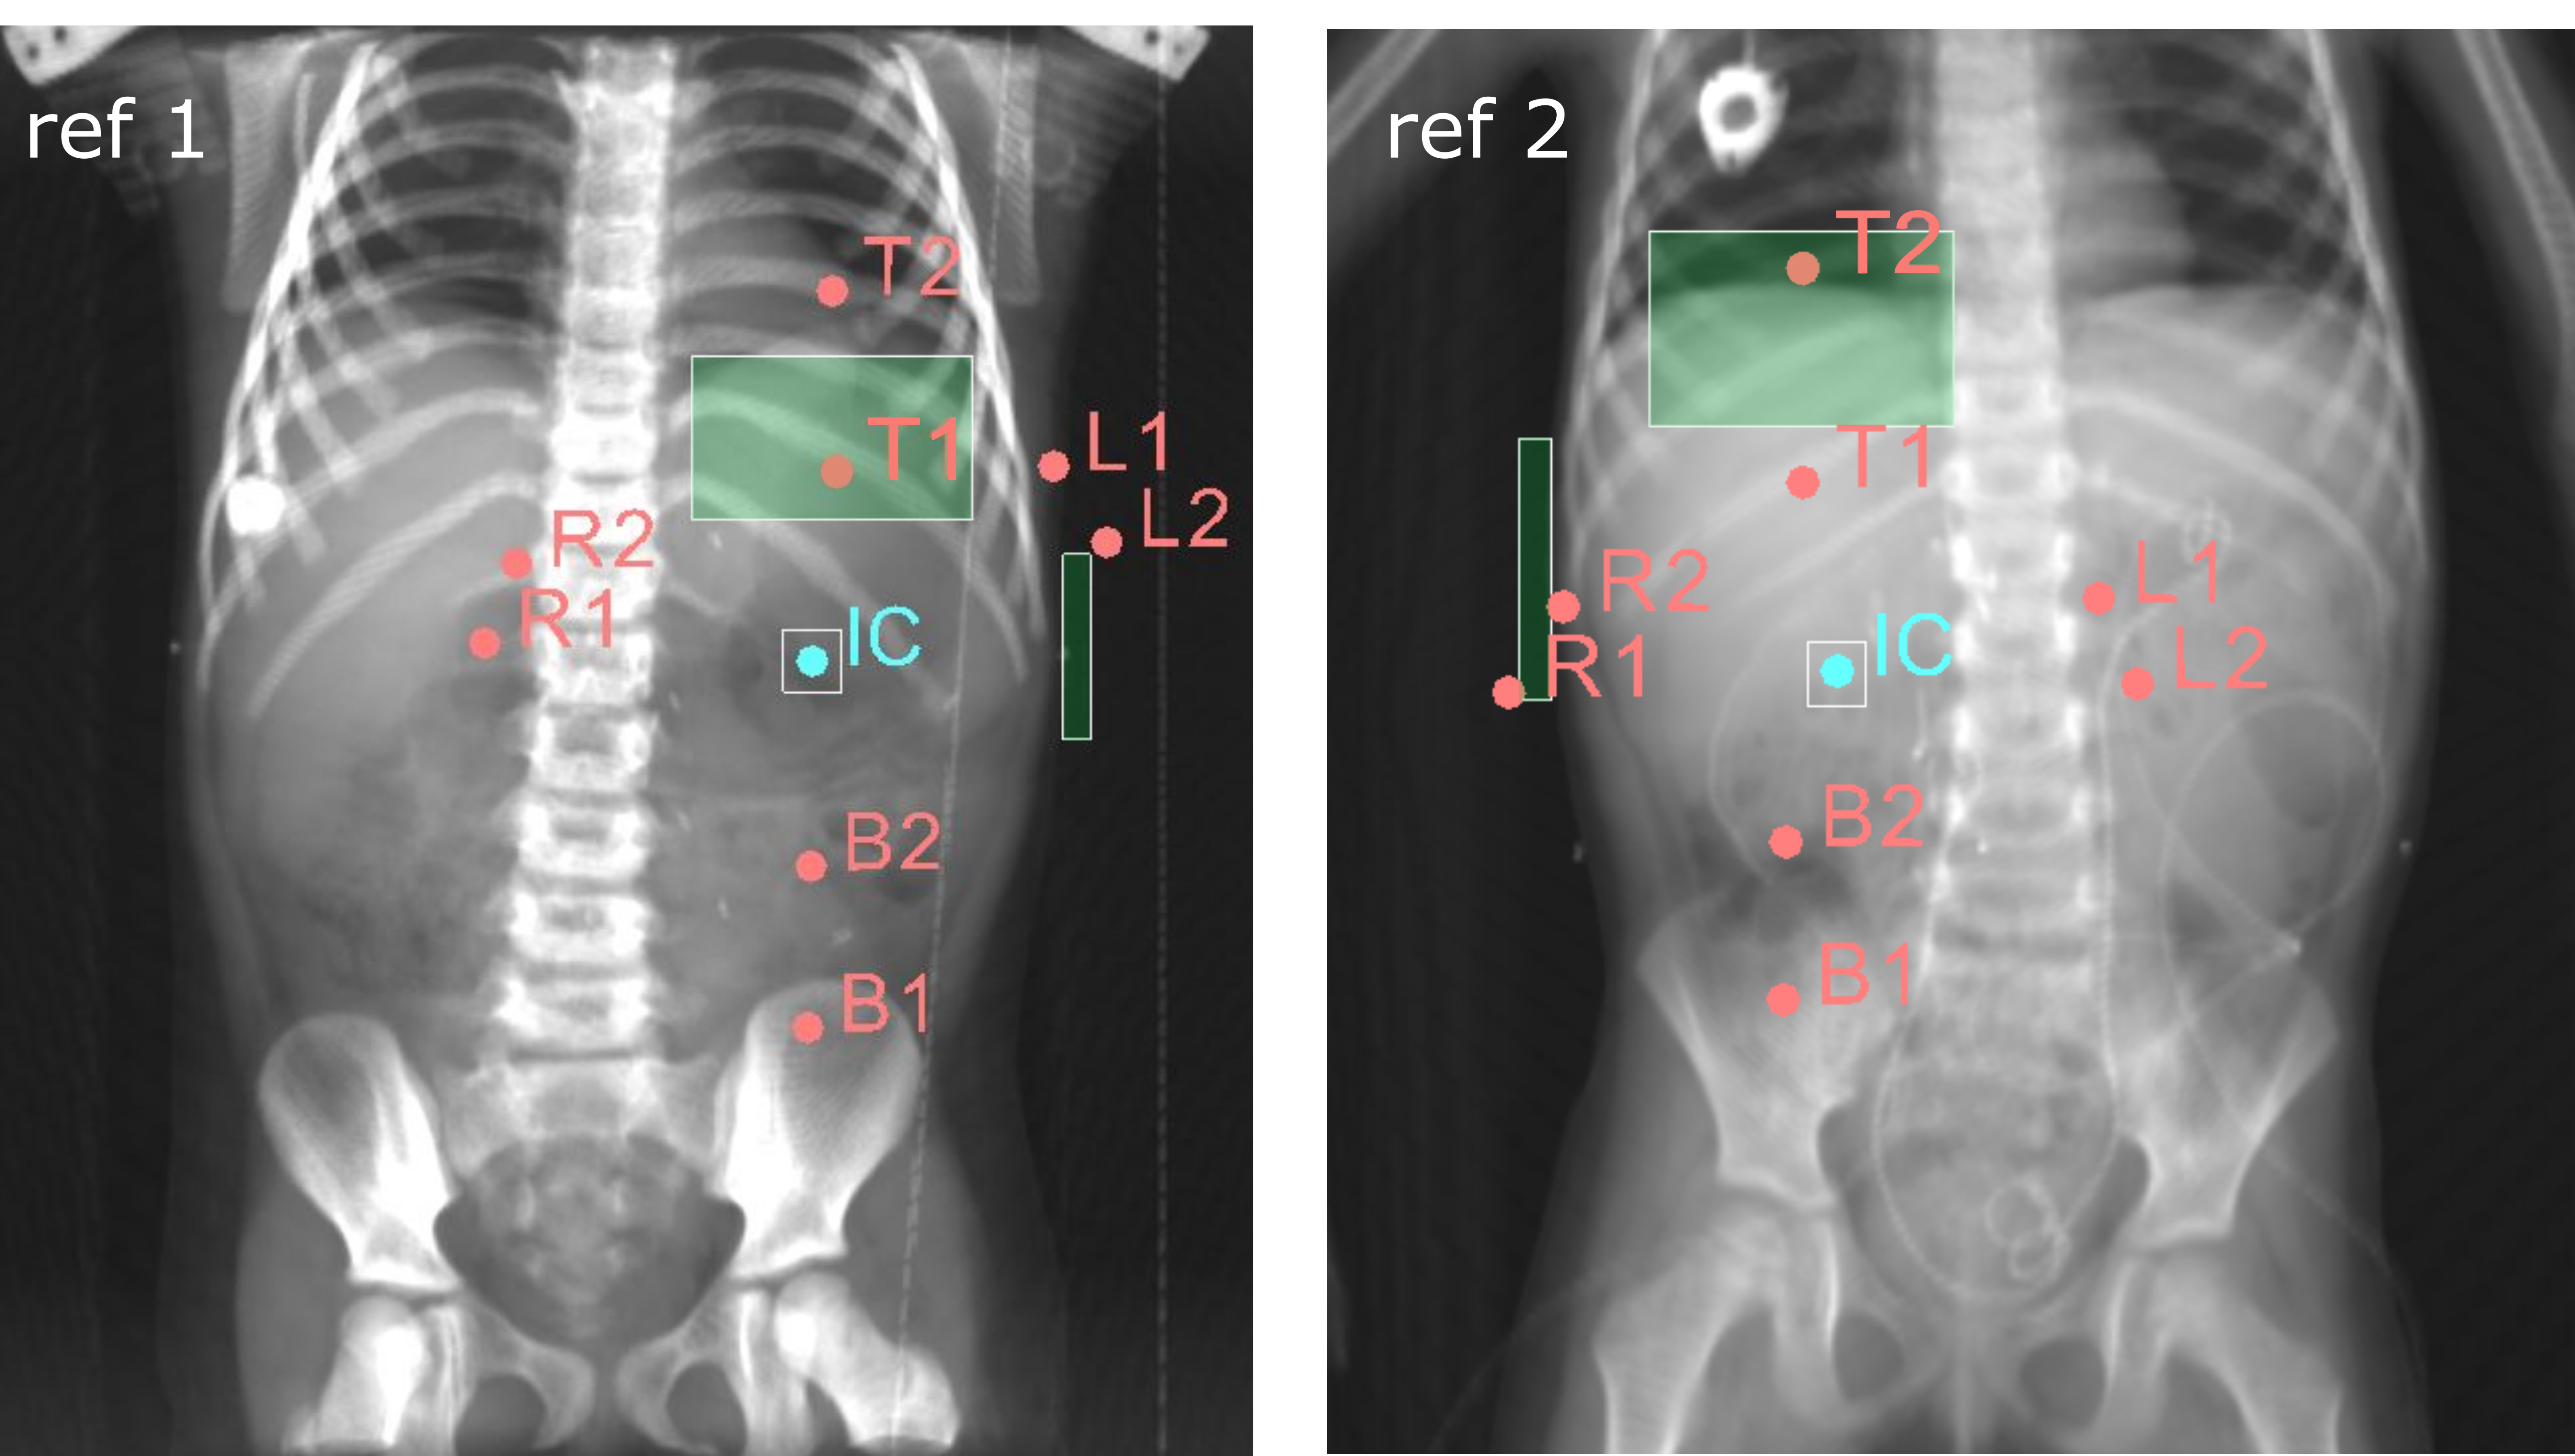

To generate artificial plans, two reference digitally reconstructed radiographs (DRRs) were considered, randomly selected from the data. One DRR was derived from a CT of a 5-year old female patient without nephrectomy (ref 1 in Fig. 2), and the other was derived from a CT of a 4-year old female patient with nephrectomy of the left kidney (ref 2 in Fig. 2). Upon these two DRRs, boundaries defining the extent of variation for clinically reasonable fields were identified by an experienced pediatric radiation oncologist (B. V. Balgobind) Note that historical clinical guidelines are slightly different from current ones (e.g., currently the iliac crests should be safeguarded, unlike in Fig. 1(c)). Figure 2 shows two examples of landmark locations identifying possible plan variations, on the two reference DRRs. Specifically, given the boundaries of possible isocenter positions and field borders, plans with a rectangular field were generated by sampling uniformly within those boundaries.

For each plan generated, an additional version of that plan including one block was generated as well. A block was simulated as the area in the upper lateral corner enclosed by the border of the rectangular field and a line crossing two randomly sampled endpoints. The endpoints were sampled from two regions roughly covering the start and end points of rib 9 and rib 12 on the DRRs (regions indicated by the green boxes in Fig. 2). This way, a sampled block covered part of the liver (in right-sided plans) or part of the spleen (in left-sided plans). All plans consisted of two opposing and symmetrical beams in AP-PA directions irradiating one side of the abdominal flank. Figures 1(b) and 1(d) illustrate two examples of sampled artificial plans (without or with a block) on respective DRRs.

For both fields with and without a block, the features representing field sizes in RL and IS directions ( and ) were set by simply considering the full rectangular area (i.e., irrespective of blocking). For fields with a block, the slope of the block (note that the block is formed by Multi-Leaf Collimators (MLCs)) and the ratio between the blocked region and non-blocked region of the field () was computed. In addition, we considered features that relate to how the plan was configured with respect to the patient’s anatomy, based on the position of the isocenter and of the bony landmarks. For instance, links the bottom of the T10 vertebra to the position of the isocenter in RL direction. Figure 4 shows an example of the anatomical landmarks and plan geometrical borders used to calculate features describing plan configuration with respect to the patient’s anatomy.